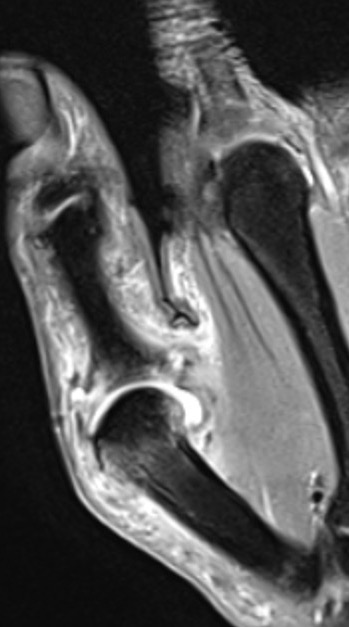

B. Displaced UCL

Coronal MRI demonstrating displaced distal UCL avulsion